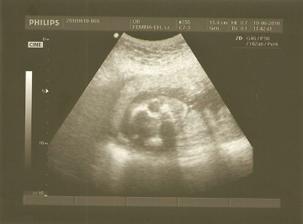

1.7.2010 - dalšia poradňa, tešíme sa....taaakže poradňa za nami, malý má už 813 g a pekne si oddychuje v brušku, ešte je stále nožičkami dole, ale hádam sa rýchlo otočí, dr. nám ešte povedala, že máme dosť nízko placentu, ale že ona sa ešte zdvihne vyššie, dúfajme.....